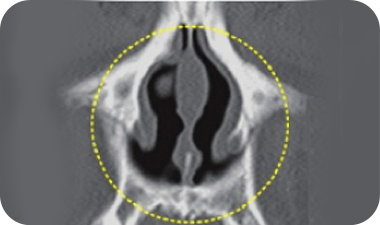

肥厚性鼻炎

鼻炎には、アレルギー性鼻炎、血管運動性鼻炎、肥厚性鼻炎などがあります。

このうち、手術によって最も確実な効果が得られるのは肥厚性鼻炎です。

鼻の内部の下鼻甲介と呼ばれる部分が異常に大きくなり、

鼻の空気通路を

塞いでいる疾患で、鼻づまり、くしゃみ、かゆみを引き起こします。

肥厚性鼻炎の

手術ノウハウ

高周波または電気熱を用いて、全体的な下鼻甲介の面積を減らし、鼻の内部の空間を広げます。